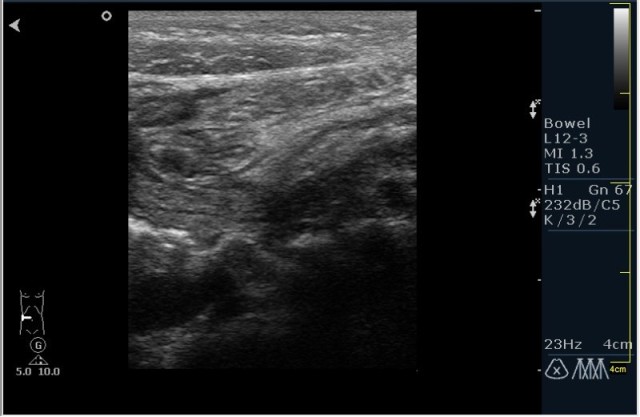

Ребёнок с болями в животе.

инвагинация! :!:

На представленных сонограммах определяется типичная "мишень" или "кокарда" (7ая и 8ая сонограмма сверху), которая при продольном сканировании превращается в "телескоп" (сонограммы 3 & 4). Все это указывет на инвагинацию кишечника (илео-цекальную). Причиной явилось лимфаденопатия брыжейки (которую вы указали). Увеличеные лимфоузлы вместе с инвагинатом хорошо различимы в просвете толстой кишки.

Уважаемые коллеги! Без сомнения имеет место илео-цекальная инвагинация.увеличенные овальные лимфоузлы, да еще такими гроздями характерны для мезаденита.Все зависит от развертывания клинической симптоматики.

Вариант 1- развите острого мезаденита спровоцировало инвагинацию.

вариант 2 - повторяющиеся эпизоды инвагинации привели к лимфоаденопатии.